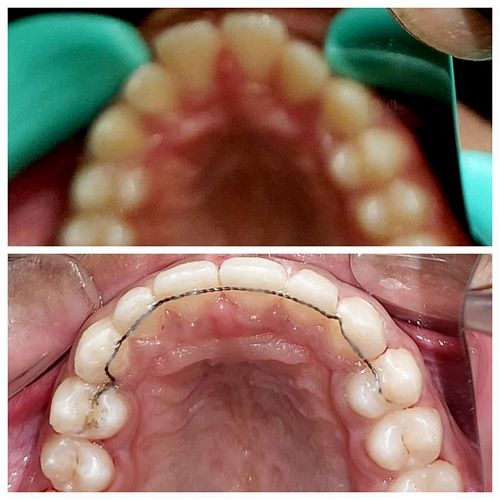

Intra-oral : Pre & Post-treatment : Maxillary Occlusal View

Intra-oral : Pre-treatment : Occlusal View

Intra-oral : Post-treatment : Occlusal View

Inta-oral : Pre & Post-treatment : Occlusal View